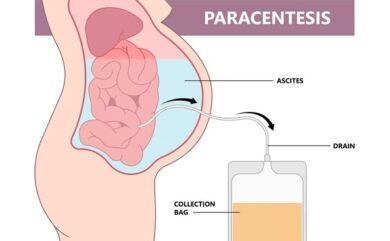

Ascitic Tapping (Paracentesis): Procedure, Uses, Benefits, and Safety

Ascites Tapping in Dehradun, Uttarakhand | Himalayan Diagnostics If you…